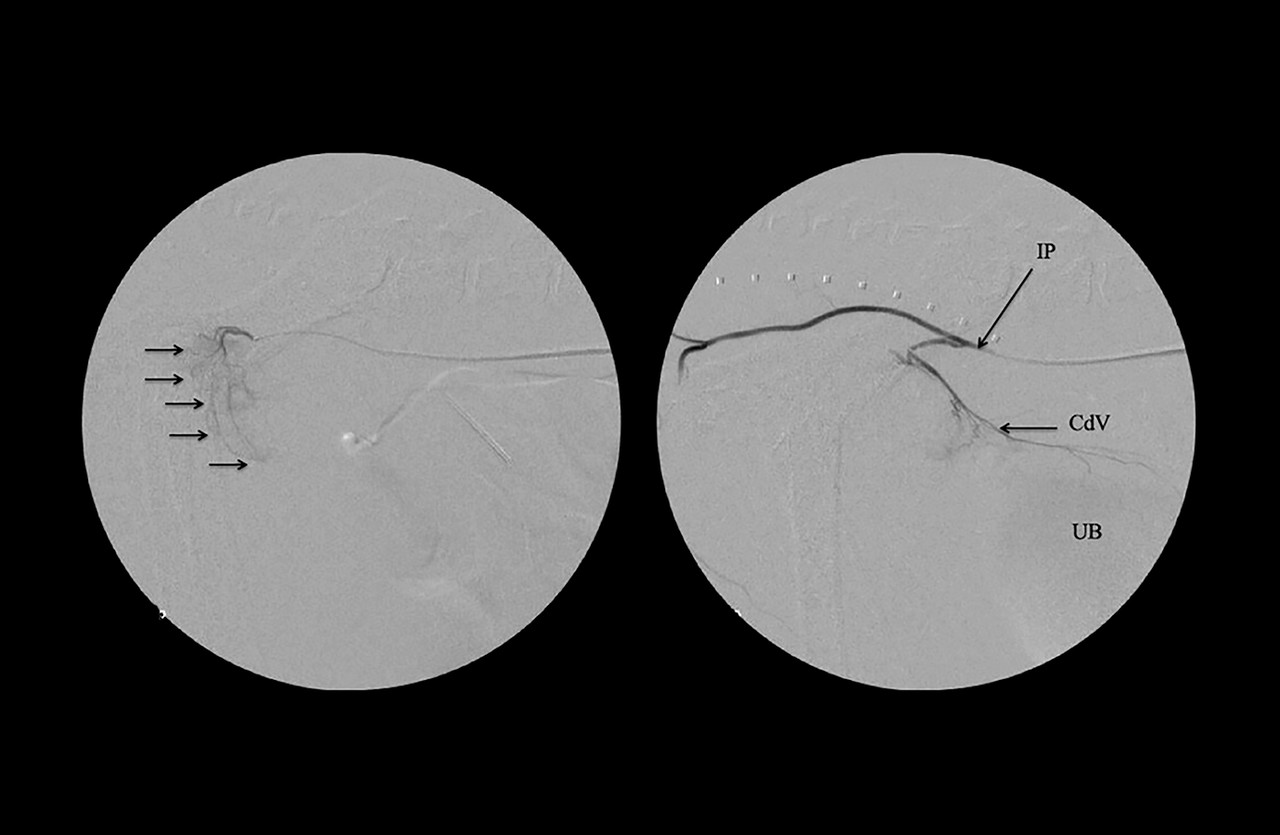

동맥색전술 (TAE), 동맥화학색전술(TACE)

동맥색전술은 종양으로 공급되는 혈관을 막아 종양의 크기를 줄여주는 시술 방법으로,

혈관의 공급만 막아주는 동맥색전술 (TAE)와 항암제가 포함된 색전물질을 이용하여 혈관을 막는 동맥화학색전술 (TACE)로 구분됩니다.

이 암치료법은 간암, 비강암, 전립선암 등에 적용할 수 있습니다.

• 동맥색전술을 통해 기대할 수 있는 효과

1. 종양의 성장을 막아 종양 크기를 줄여줍니다.

2. 종양의 파열로 인한 출혈을 예방해 줍니다.

3. 종양으로 인한 통증을 완화시켜 줍니다.

• 동맥색전술은 어떤 아이들에게 적용할 수 있을까요?

수술적으로 종양 제거가 어렵거나 위험한 경우

동맥내 항암요법 (IAC)

동맥내 항암요법은 종양 부위에 직접적으로 항암제를 주입하는 방법으로, 일반적인 항암요법에 부작용이 심하거나 효과가 낮은 경우에 적용할 수 있습니다.

이 암치료법은 방광암, 전립선암, 안내암과 같이 항암치료에 반응이 낮은 종양에 주로 적용됩니다.

치료 반응에 따라서 3-4주 간격으로 최대 5회 시술합니다.